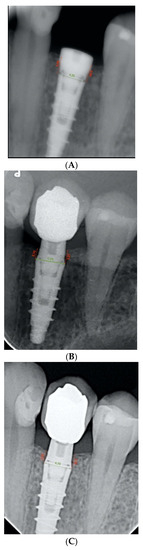

The bone level was measured as the linear distance between the implant–abutment interface and the level of the crestal bone margin, mesial and distal to each implant, all calculated in millimeters. Therefore, this distance was analyzed both mesially and distally on the day of implant placement surgery. Subsequently, the distance of the same points was measured on the radiograph on the day of prosthetic restoration placement. At this point, the first bone loss figures were obtained by calculating the difference between the heights recorded. The same measurements were taken, but on the control radiographs, after one year of prosthetic loading, and the peri-implant bone loss was calculated in relation to the day of implant placement surgery. At this point, the second bone loss figures for the study were obtained (Figure 6A–C).

Figure 6. (A) Periapical radiograph of an infracrestal implant (Shelta) on the day of surgery. (B) Periapical radiograph of an infracrestal implant (Shelta) after 1 year of prosthetic loading. (C) Periapical radiograph of an infracrestal implant (Shelta) on the day of prosthetic placement, 4 months after surgery.